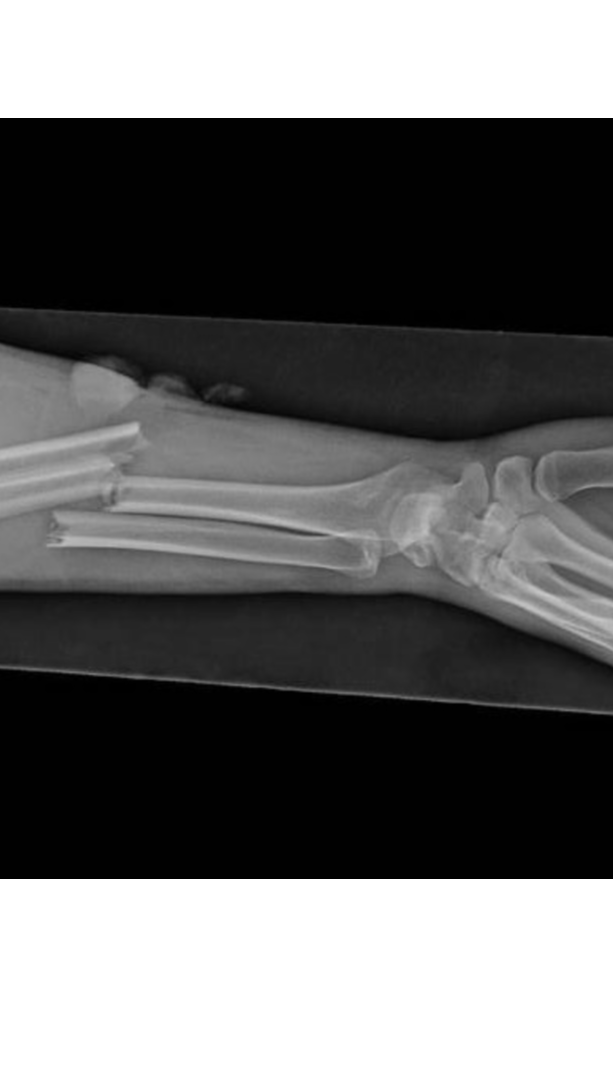

Hi everyone. I wanted to reach out and see if anyone might be able to help this gentleman who lives in Zarqa, Jordan. (I will keep his name anonymous for privacy purposes; but I can vouch that I personally know him). His 10 year old son fell and shattered his arm. He took him to the community (free) hospital (مستشفة الحقومه) and they told him that his son’s surgery would be out of their scope and that he needed to take him to a more advanced facility for surgery. So he took him to a “private” hospital in Jordan that demanded a certain amount of money before performing surgery. (In places like Jordan, in private hospitals you have to pay BEFORE your care) So naturally, seeing his son in the shape that he was in, he begged the hospital to perform the surgery under the promise that he would pay them back by weeks end. Which leads me to this Gofundme. I know many of you have been so generous this past year in particular. We are so incredibly blessed in so many ways. I reach out to my tribe to see if we can continue to help others in need. I’m trying to raise 1500 in the next few days in order to cover the boys surgical costs. The father whatsapped me in the middle of the night saying he was in the mosque praying that God would help them in their time of need. Please help me help them make their prayers become a reality. Thank you for your kindness, love and generosity in advance